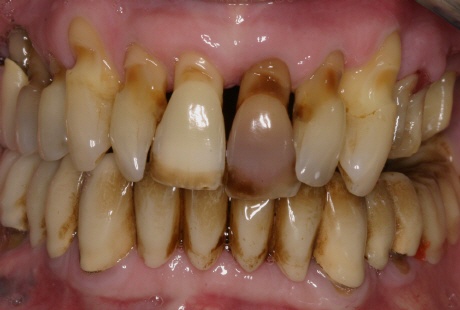

Bild der Zerstörung

Durch mikrobielle Beläge (vor allem agressive Bakterien, sogenannte "Killerkeime") kommt es zum Abbau des gesamten Zahnhalteapparates. Die Folgen: die Zähne werden optisch immer länger und immer beweglicher, bis letztenendes das ganze "Kartenhaus" zusammenfällt.